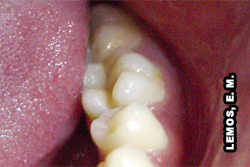

Por vezes, durante a inspeção clínica com o uso do espelho e explorador é possível constatar fraturas coronárias e/ou radiculares, porém em alguns casos, necessário se faz, lançar mão de recursos alternativos, como o teste de mordida com instrumentos oclusais para melhor investigar a possibilidade de fraturas (completas ou incompletas) sem alterações clínicas visíveis em dentes com sensibilidade à mastigação. A radiografia periapical nesses casos não permite visualizar ou interpretar tais fraturas, salvo se os fragmentos estiverem separados. Dente 25 apresentando fratura proximal oblíqua oclusal-palatina e, dente 26 fratura da restauração em amálgama. Uma cunha de madeira foi colocada no dente 25 para afastar os fragmentos durante a tomada fotográfica, figura ao lado.

![]() |